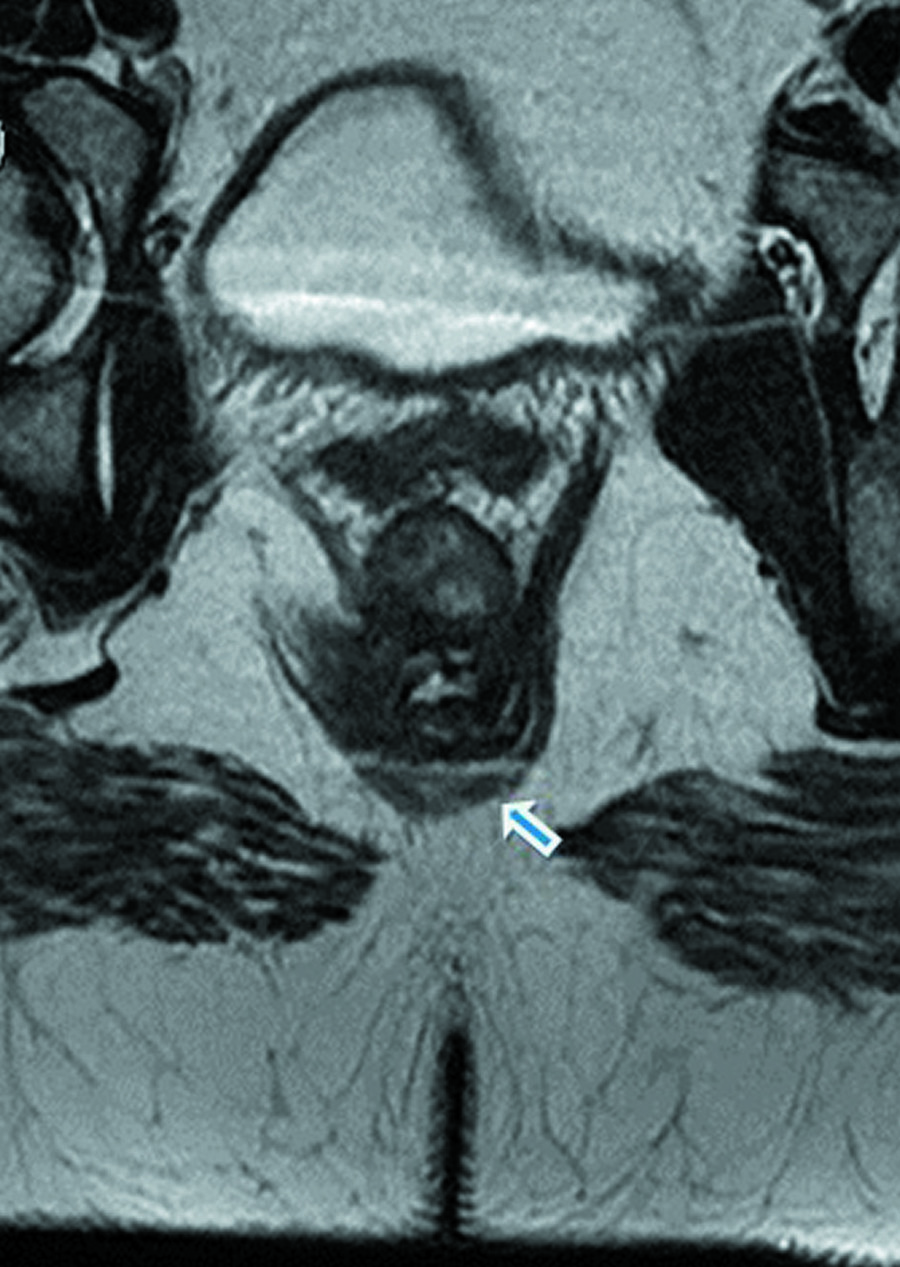

Los médicos dieron a conocer el hallazgo a través de una publicación en el Journal of Medical Case. El informe detalla que la paciente tenía una rara formación del tracto digestivo, lo que generó el segundo canal anal.

“La duplicación del canal anal es la malformación congénita del tracto digestivo más extraña. Cerca de 60 casos han sido descritos alrededor del mundo”, detallan en la investigación publicada por los médicos.